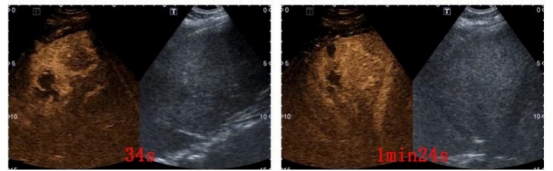

杨秀华对葛某的肝脏进行全面扫查,共检出6枚病灶,分别位于肝S3、S5(与胆囊及门静脉分支位置近)、S6和S7(位置近膈肌、受气体干扰,且治疗过程易损伤),病灶多且位置刁钻成为了治疗的难点,如何在保证安全的前提下对全部病灶进行治疗,成为此次治疗的难题,杨秀华与李林强本着为患者谋求最大益处的治疗原则,决定为葛某行射频消融治疗,一次性消融全部病灶。术前杨秀华团队姜脉涛医生先在超声引导下为葛某建立人工胸水,在麻醉医生紧密配合下,杨秀华凭借丰富的治疗经验,精准布针,仅用2根射频针便完成6枚病灶的完全消融。

射频后病灶完全消融